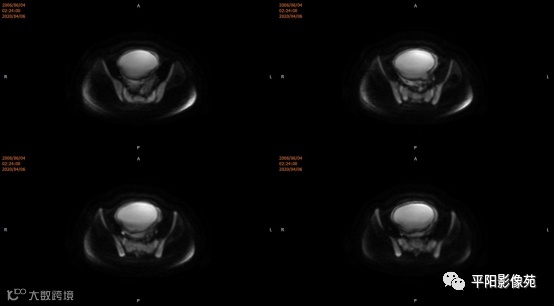

患者,女,13岁

主诉: 下腹部胀痛2+月,加重1天

现病史: 患者月经未来潮,2+月前无明显诱因感下腹部憋胀,间断胀痛,可忍耐,伴排便困难,自认为便秘引起腹胀,未在意。近1+月腹胀、胀痛次数增加,觉下腹部逐渐增大,小便正常。

您的诊断?

宫颈缺如、阴道闭锁

3.CT检查 对子宫、阴道的界限区分有一定限制,对子宫内膜、肌层难以分辨,故CT对子宫先天性异常的研究较少。阴道闭锁时,若宫腔内经血潴留,可见液性低密度聚集,子宫肌层密度均匀。

4.MRI检查 对软组织分辨率好,能够清晰区分子宫及阴道,对子宫内膜、结合带、肌层可清晰分辨;能明确子宫、宫颈、阴道结构异常的部位、范围、性质等。宫腔内经血潴留时,宫腔内见短T1长T2信号。